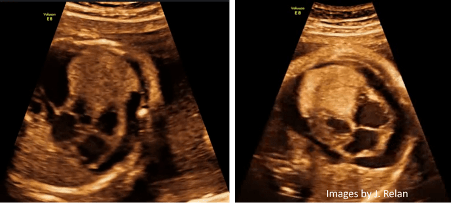

Fetal echo of a 29 weeks fetus showing large Rhabdomyoma causing heart failure and pericardial effusion. A pericardiocentesis was done at the 29th and 33rd weeks and the pregnancy was completed (37 weeks). The baby was given Sirolimus after delivery, and the rhabdomyoma improved. ( JACC: Case Reports Volume 3, Issue 13, 6 October 2021, Pages 1473-1479; Jay Relan et al)